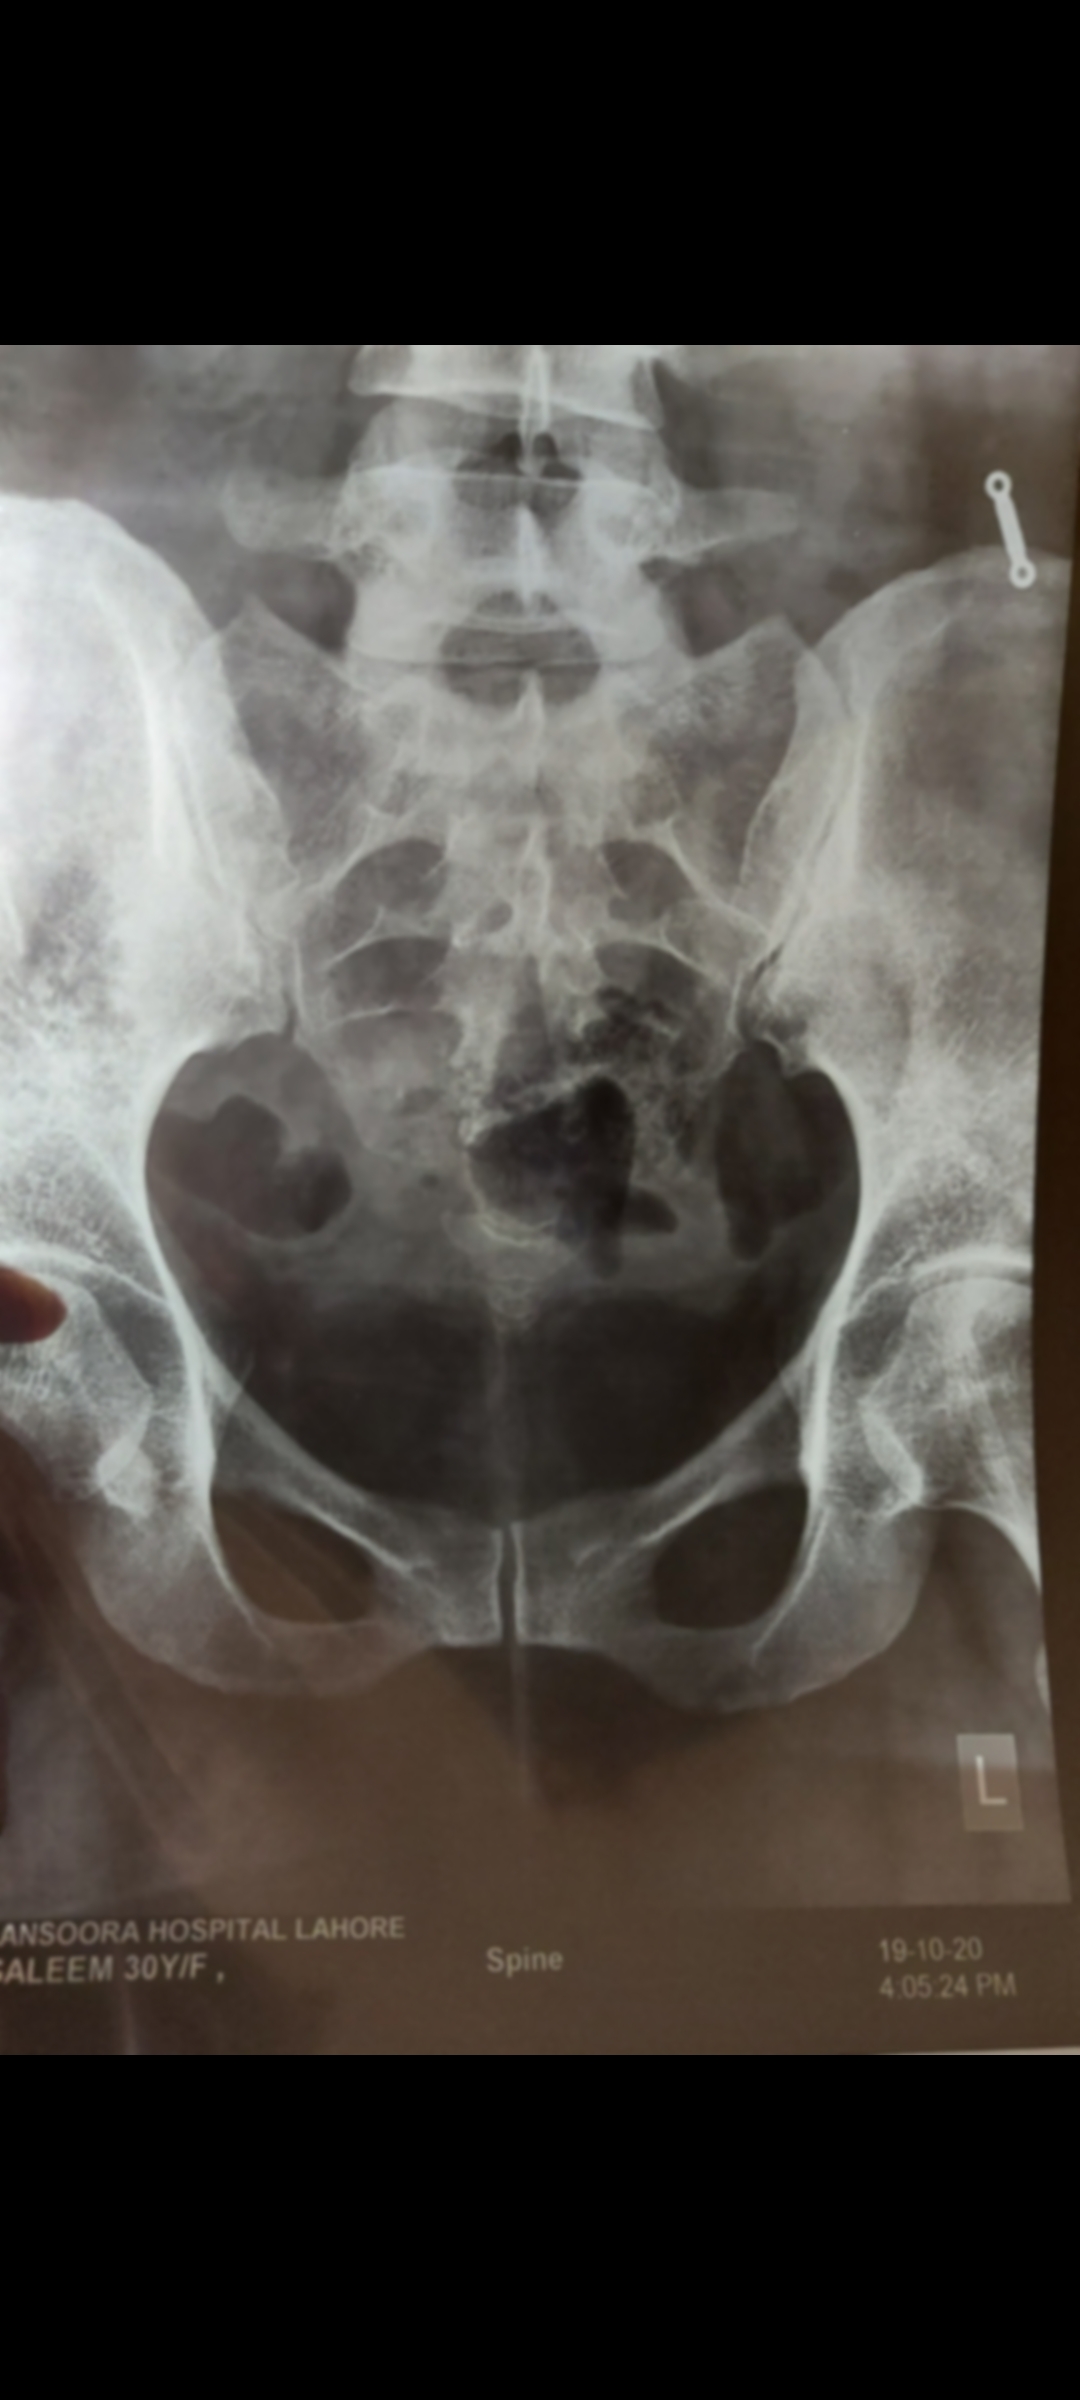

I have pain in my tail bone. Now I have when I sit or stand or lay on bed. Doc said its inflammation HISTORY--> tailbone was injured by falling 2 times at the same spot 5 years ago. I had that similar pain always while sitting or standing for long time but now it has increased n its very painful cant sit in my class. XRAY ATTACHED Thank you in advance

Most likely it is Coocydynia, You should avoid sitting on hard surfaces, use air cushons and take painkiller when required

It’s called Coccydynia meaning pain in the tail bone . Treatment is care , use coccyx donut cushion while sitting and anti inflammatory medicines like Neoprox 500 mg twice daily if there is pain for a few weeks . It it still don’t work then you can proceed with Local steroid injection in the coccyx area. Last option is surgical excision of the involved segment.